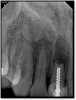

Fig 14. The post was shorter than ideal.

Figure 14

The rules for placement of a post depend on good retention: the greater the length, the greater the retention.3 Also, two-thirds of the length of the root is ideal, but 4 to 5 mm of apical gutta-percha is essential because anything less than that will disrupt the seal.8 Figure 14 shows a case where a patient had a post, core, and crown. The threaded post was shorter than ideal because the tooth was longer. Not visible was the mental foramen underneath. The patient did not have the financial resources to have the case redone. However, when the post would be removed, the clinician would need to trephine or use an ultrasonic around it, making the access bigger than an ideal conservative access. Potentially, the crown would come off. The patient did not have finances for re-treating the tooth and could not have an apicoectomy because the mental foramen was directly under the tooth.